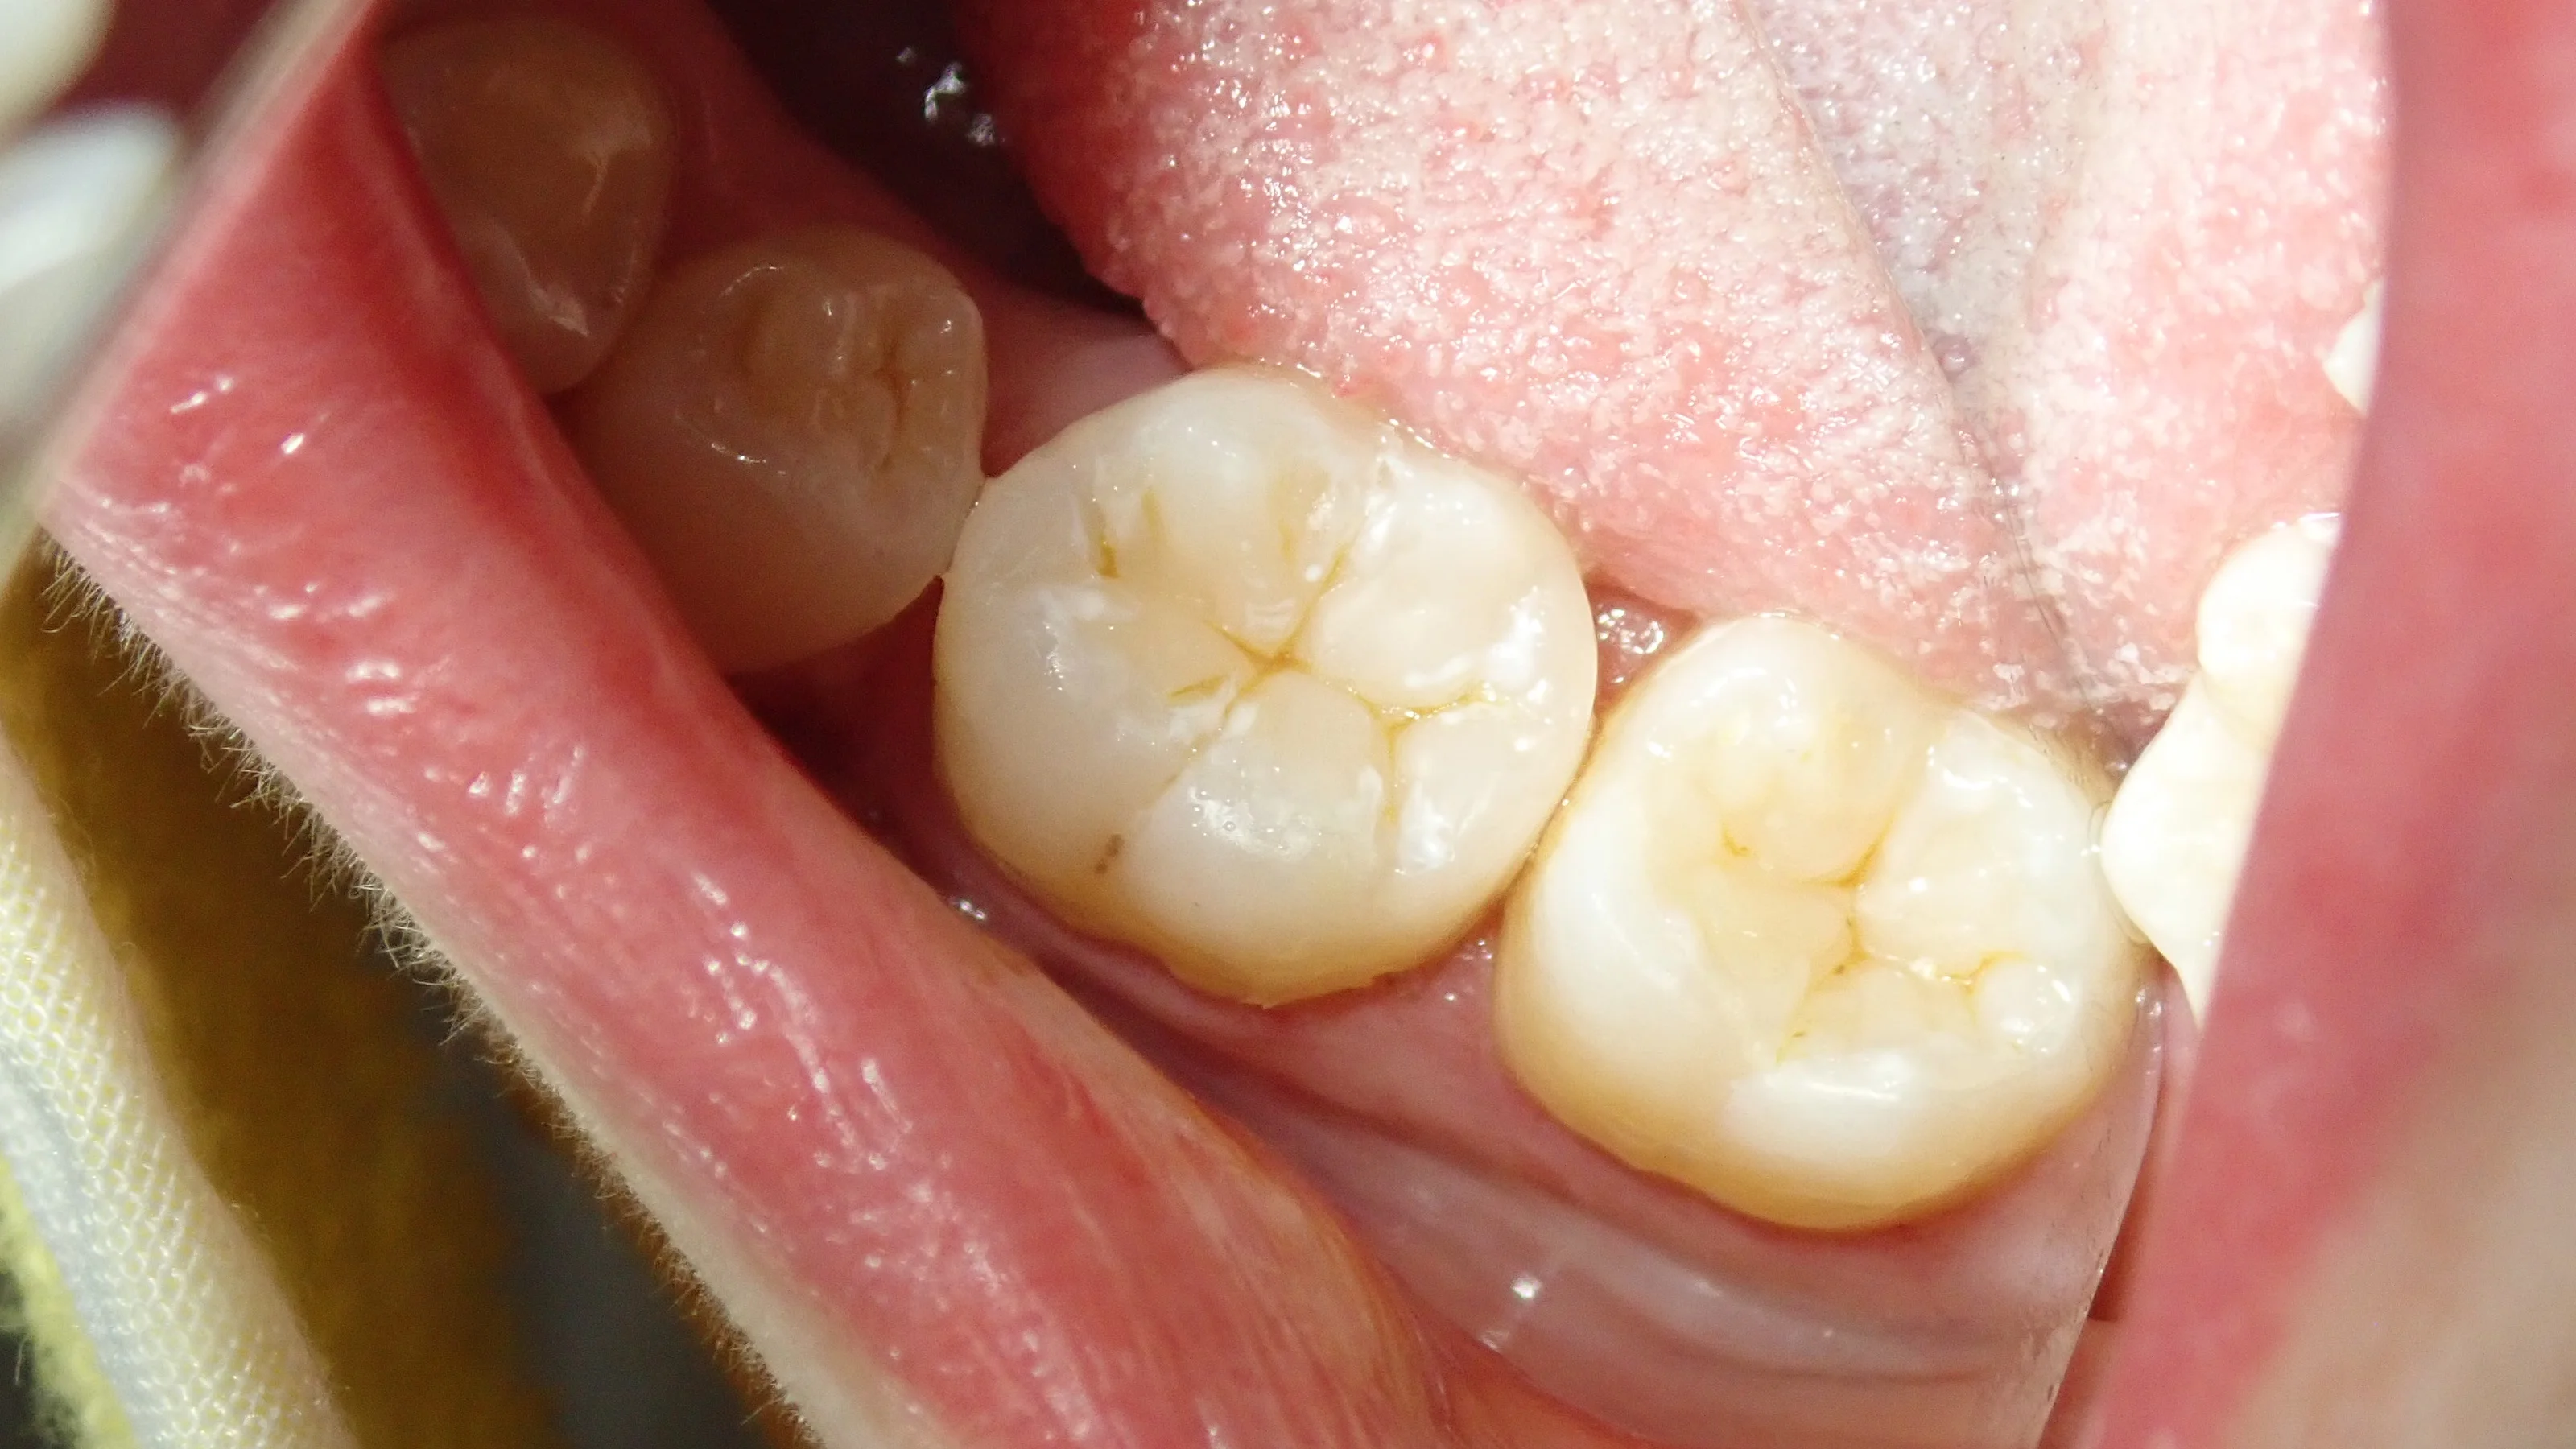

術前がこちら

奥2本のダイレクトボンディング|坂寄歯科医院(取手市藤代) - 画像4

手前の歯との間は矯正の後戻りによって隙間が開いている状況になっています。